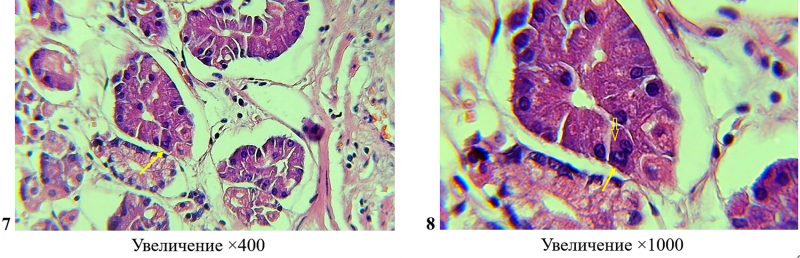

Операционный препарат резецированного тела желудка по поводу умеренно-дифференцированной аденокарциномы. Фото 7-8: в фундальных железах, вблизи опухолевой ткани имеется главная клетка, имеющая морфологические признаки гетерокариона гибридного происхождения (показана стрелками). Окраска гематоксилином-эозином.